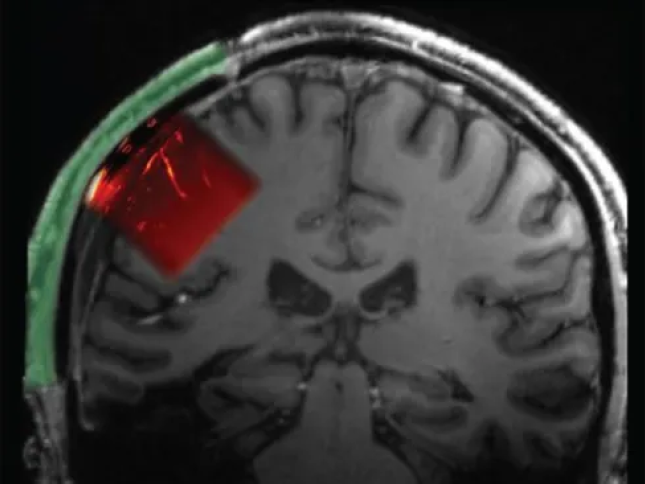

تکنولوژی کاشت پنجره در جمجمه برای درک افکار با استفاده از فراصوت این دادهها به دانشمندان امکان داد از آنچه در مغز این مرد میگذشت، تصویری تولید کنند؛ شبیه به آنچه هنگام سونوگرافی جنین در شکم مادر انجام میشود مغز هنگام خواب سعی میکند آینده را پیشبینی کند مقاله دانشگاه هاروارد: فرازمینیها ممکن است در قالبی شبیه انسان و در میان ما زندگی کنند نخستین پیوند قرنیه مصنوعی جهان با موفقیت انجام شد